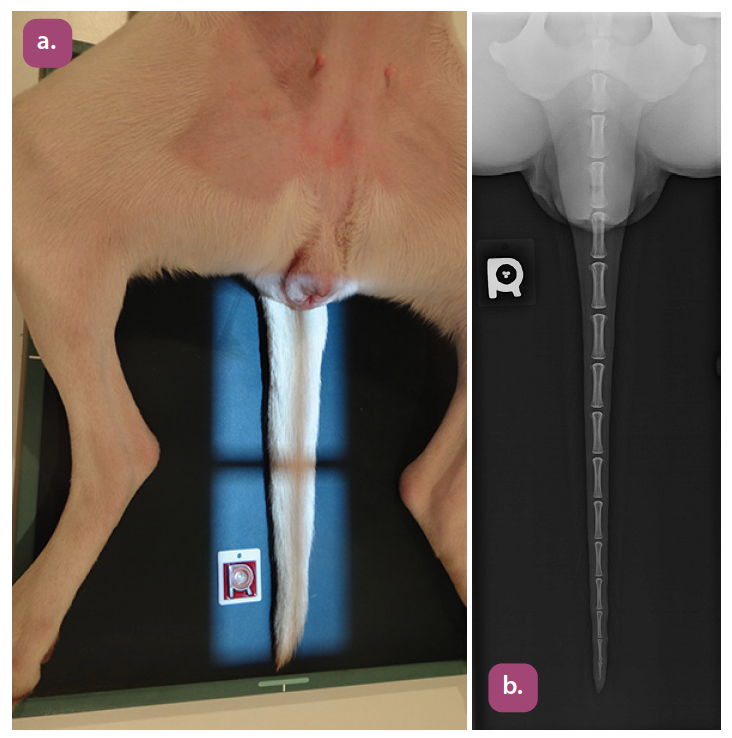

ventrodorsal coccygeal spine projection

lateral coccygeal spine projection